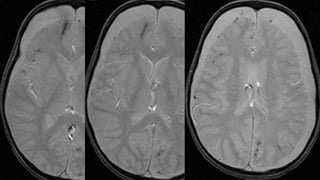

Este documento presenta el caso de un niño de 3 años que sufrió episodios de paresia y alteraciones neurológicas. Exámenes revelaron la presencia de un higroma cerebral que fue drenado. A pesar de una mejoría inicial, el niño continuó presentando síntomas neurológicos intermitentes. Exámenes posteriores identificaron una rara vasculopatía que afecta vasos cerebrales y otros órganos, con un pronóstico grave.